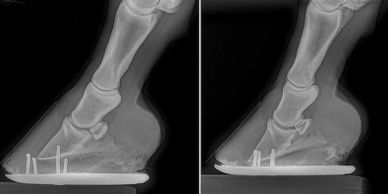

Radiographs, commonly known as x-rays, are often taken during lameness exams to visualise the bones and joints. Portable digital systems (DR) are mostly used for lower limb examinations and are especially useful if it is difficult or unsafe to travel an injured horse. This can be done in your yard.